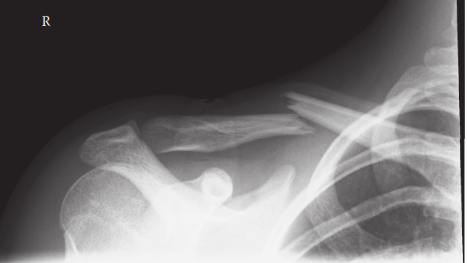

A 35-year-old woman fell from a ladder, injuring her right shoulder. These are her radiographs. 1. What do th…

A 32-year-old woman is admitted after a fall from her bicycle. She has an isolated injury to her left upper l…